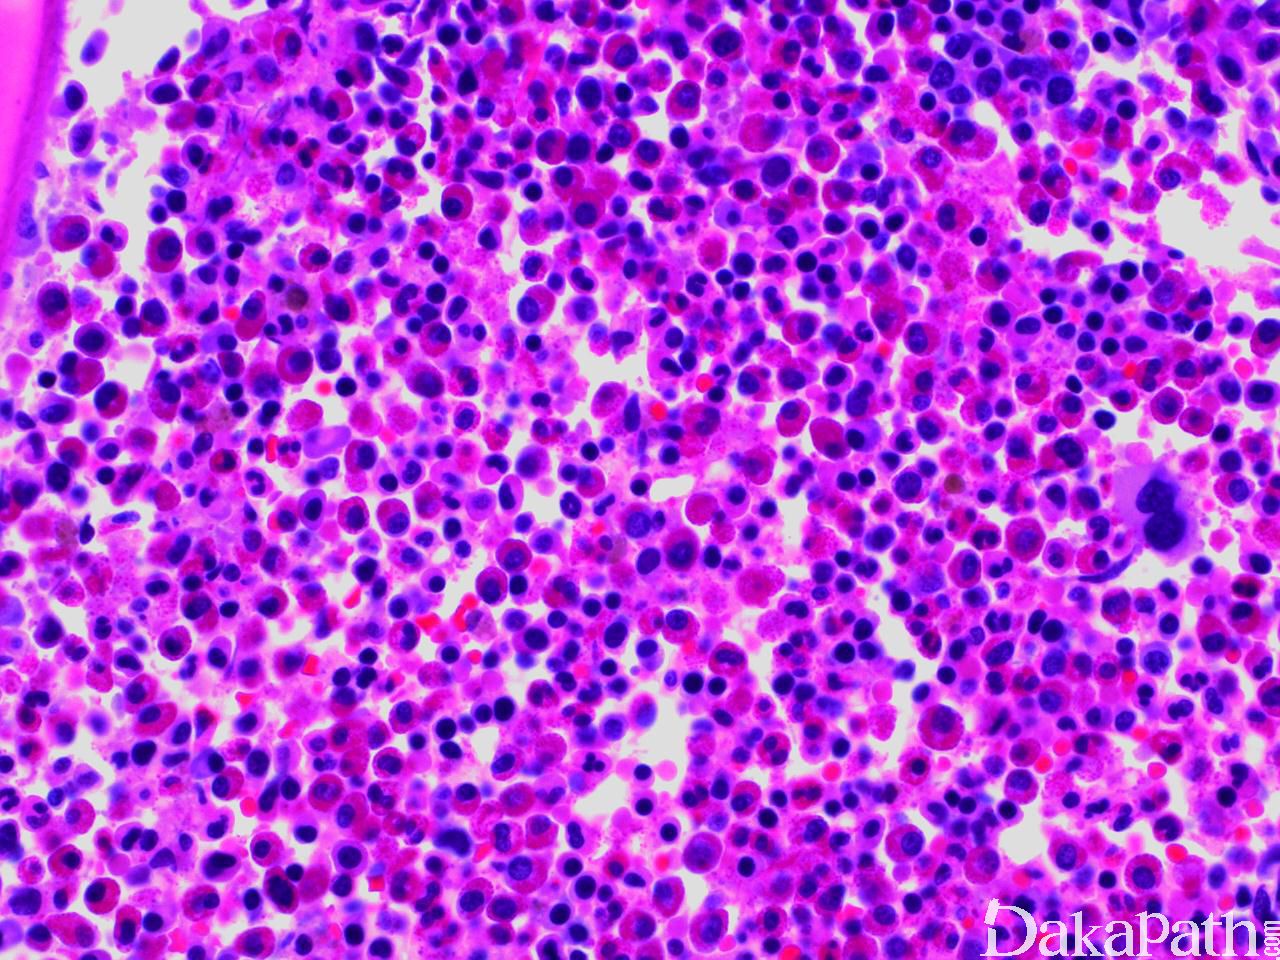

CEL NOS 最突出的特征是外周血嗜酸细胞增高,主要为成熟细胞,仅有少量嗜酸性中幼粒细胞或早幼粒细胞。可有不同程度的嗜酸细胞异型,包括颗粒稀少(胞质透明区),胞质空泡,核分叶过多或减少及核增大。但这些改变都可见于反应性嗜酸细胞增多,对诊断没有帮助。偶尔 CEL NOS 嗜酸细胞形态正常,但无异型增生通常支持反应性改变。

常伴中性粒细胞增多,有时伴单核细胞增多,伴轻度嗜碱性粒细胞增高也有报道。可以见到原始细胞,但<20%。

骨髓细胞密度增加,部分原因为嗜酸细胞增生,大多数病例嗜酸细胞分化成熟正常。红系和巨核系一般正常。

母细胞比例增高(5-19%)支持 CEL,NOS;同样,其它系异型增生也支持 CEL,NOS。